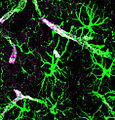

- Astrocyte.

- Irregular non-ovoid nucleus - key feature.

- Nuclei less dense than in oligodendrocyte.

- Close to blood vessels.

- Form blood-brain barrier.

- Cytoplasm normally not visible.

- Image: astrocyte (med.unsw.edu.au) (in endocrine development).